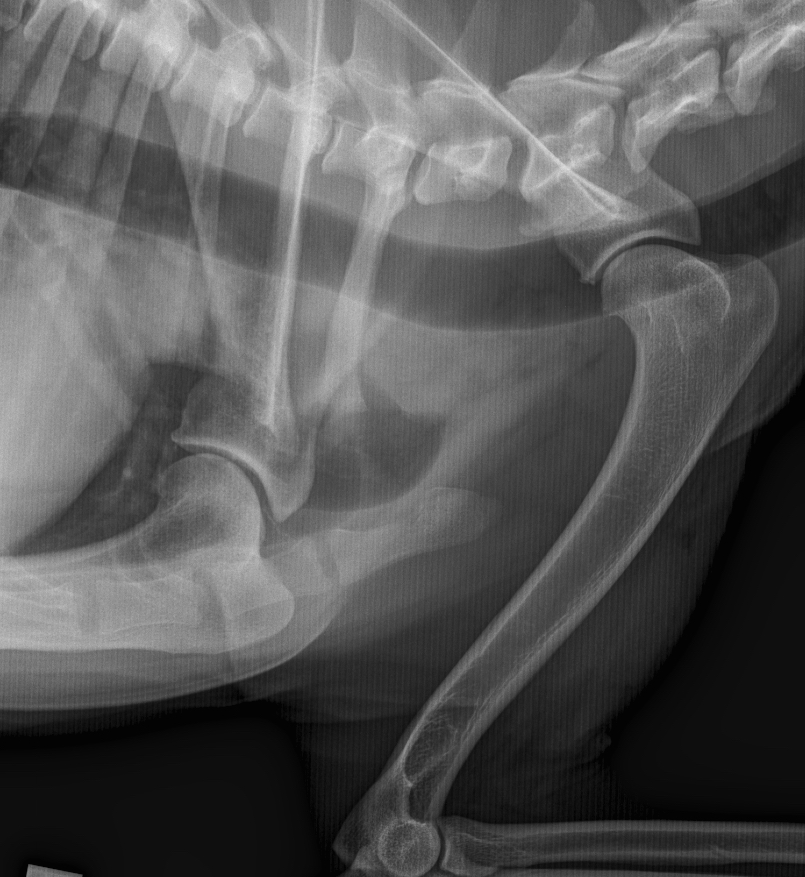

I början av 2018 började Timi plötsligt halta på sitt ena framben. Det hade inte hänt något som kunde förklara hältan. Timis ägare tog därför Timi till veterinären där Timi röntgades. Röntgenbilderna visade en tydlig orsak till hältan – Timi hade artros i båda boglederna. Förändringarna i lederna var inte än stora men såpass tydliga att allt hoppande måste få ett slut. Veterinärens råd var ändå att fortsätta med rask motion eftersom en bra muskelmassa stödjer lederna.